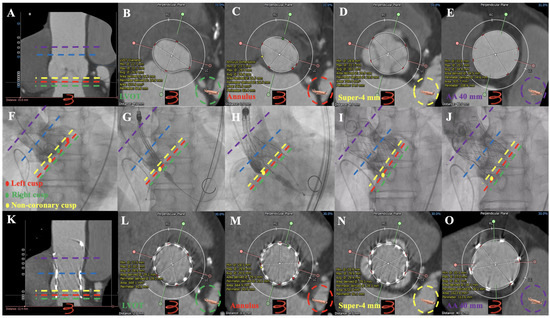

3.2. MDCT Evaluation and Anatomical Classification

3.3. Operation